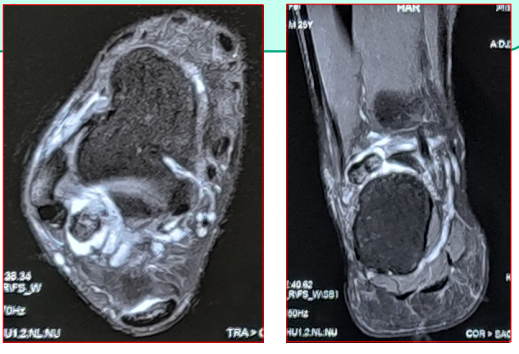

疼痛性距后三角骨。川汇区杨脑村人 男、25岁、散打运动员,比赛后疼痛一周,加重三天, 无法行走。

保守治疗:消炎、止痛类药物应用,休息,深部热疗 一周,症状消失。